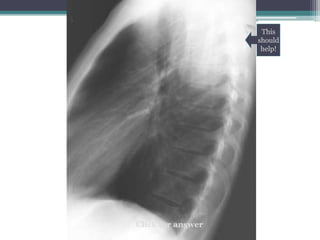

This

should

help!

โ€ข Answer: Mass is in posterior mediastinum. We

know because it remains sharply outlined in apex of

thorax, indicating that it is surrounded by lung.

โ€ข This particular example is a ganglioneuroma